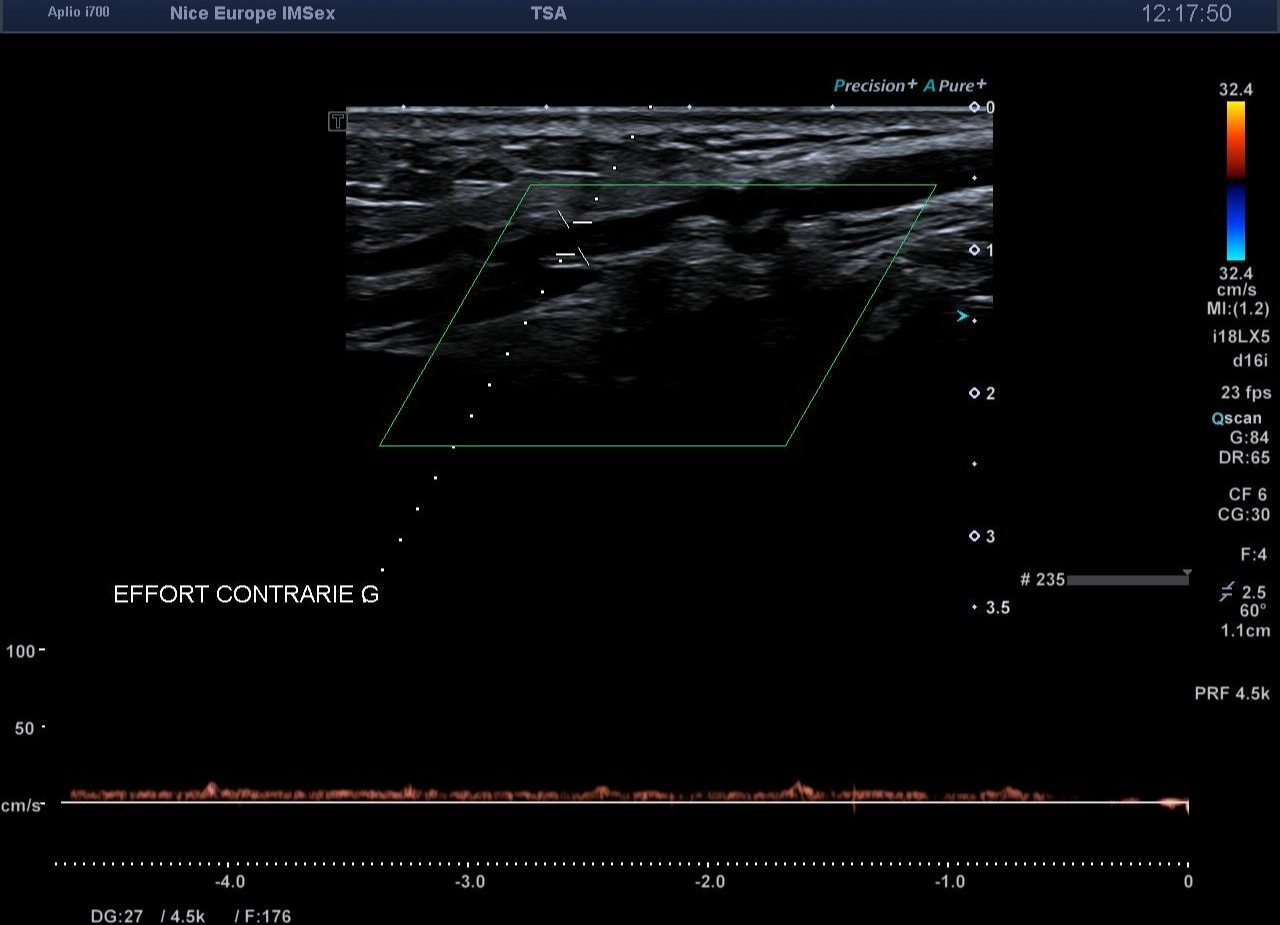

Devant ce morphotype athlétique et la négativité de l'examen statique, un test de provocation par échographie dynamique est entrepris pour rechercher un syndrome de l'artère poplitée piégée (ou piège poplité). Lors d’une manœuvre de flexion plantaire contrariée (mise en tension soutenue des muscles de la loge postérieure contre résistance), on objective en temps réel :

1. 1. Une compression extrinsèque majeure de l’artère poplitée par les chefs musculaires gastrocnémiens.

2. 2. Une occlusion artérielle complète (diastolique et systolique) au point de compression.

3. 3. Une abolition du flux artériel distal.

Lors de la mise en évidence d'un arrêt de flux artériel au niveau poplité, il est d'usage de documenter le retentissement sur les artères de jambe. Toutefois, l'analyse du flux de l'artère tibiale postérieure (ATP) lors de cette manœuvre constitue un piège diagnostique bien connu.

En effet, lors d'une contraction isométrique maximale chez un sujet présentant une hypertrophie musculaire sévère, l'augmentation spectaculaire de la pression intramusculaire dans la loge postérieure profonde peut entraîner une compression locale de l'ATP, indépendamment de toute sténose poplitée en amont. Cela génère un "faux positif" hémodynamique.

Pour confirmer de manière spécifique que l'occlusion siège bien au niveau du creux poplité, l'échographiste doit interroger l'artère tibiale antérieure (ATA). Cheminant dans la loge antérieure de la jambe, l'ATA est soustraite à l'hyperpression de la loge postérieure. Si le flux de l'ATA s'effondre lors de la flexion plantaire contrariée, cela atteste formellement que l'obstacle artériel se situe en amont, signant ainsi le piège poplité

• Spécificité du retentissement distal : L'arrêt du flux sur l'artère tibiale antérieure (ATA) lors des manœuvres de provocation est le témoin fiable et spécifique d'une occlusion poplitée extrinsèque.